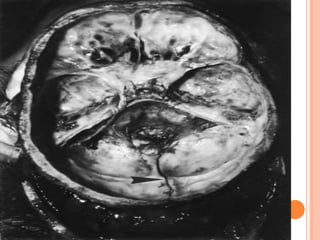

mli1. Evidence of application of blunt force. Accidental Homicidal Suicidal – Unusual ARTIFICIAL BRUISES 2. Though in itself a trivial injury, Lies in the site & the organs involved. Contusion of vital organs heart and brain.Caused marked derangement of functions & even death

complications1. Contusion contain 20- 30 ml of blood or even more. Multiple contusion can cause death from shock & internal haemorrhages.2. Gangrene & death of tissue.3.Good site for Bacterial growth.

Internal bleeding due to ruptures of vessels and bleeding into body cavities – like pericardium, peritoneum, pleura and cranium.  Causes of death due to injury:

mli1. Evidence ofapplication of blunt force. Accidental Homicidal Suicidal – Unusual ARTIFICIAL BRUISES 2. Though in itself a trivial injury, Lies in the site & the organs involved. Contusion of vital organs heart and brain.Caused marked derangement of functions & even death

complications1. Contusion contain20- 30 ml of blood or even more. Multiple contusion can cause death from shock & internal haemorrhages.2. Gangrene & death of tissue.3.Good site for Bacterial growth.

Internal bleeding dueto ruptures of vessels and bleeding into body cavities – like pericardium, peritoneum, pleura and cranium. Causes of death due to injury: